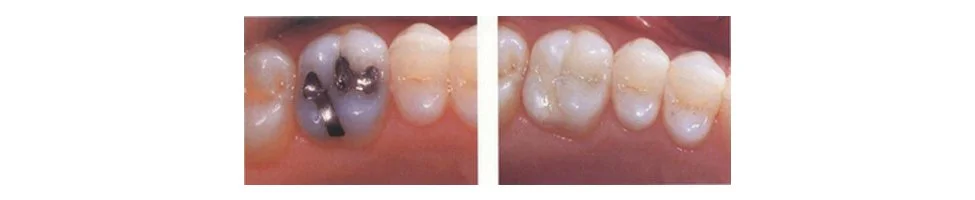

Composite Fillings

A composite resin is a tooth-colored mixture containing silicon dioxide glass as filler. Originally, these bonded fillings were confined to the front teeth because they were not strong enough to withstand the pressure and wear generated by the back teeth.

- New advances in materials have allowed composites to be successfully placed in the back teeth as well. Composites are not only used for restoring decay but are also used for cosmetic improvements of the smile by changing the color of the teeth or reshaping disfigured teeth.